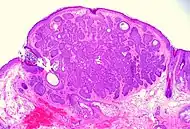

| Fibroepithelioma of Pinkus | Anastomosing epithelial strands in a fenestrated pattern[34] | Most commonly occurs on the lower back.[30]: 748 [31]: 648 | ![]() |